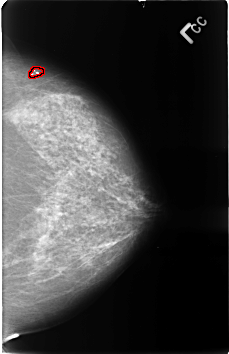

FILE: B_3406_1.RIGHT_CC.OVERLAY

TOTAL_ABNORMALITIES 1

ABNORMALITY 1

LESION_TYPE CALCIFICATION TYPE PLEOMORPHIC DISTRIBUTION CLUSTERED

ASSESSMENT 4

SUBTLETY 3

PATHOLOGY MALIGNANT

TOTAL_OUTLINES 1